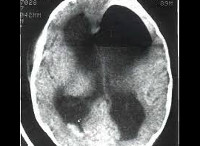

Поскольку пневмоцефалия не имеет специфических клинических проявлений и в половине случаев наблюдается ее субклиническое течение, то диагностировать ее клинически неврологу и нейрохирургу практически невозможно. Интракраниальное наличие воздуха может быть выявлено при рентгенографии черепа. Для диагностики основной патологии, определения локализации и размеров воздушного пузыря целесообразно проведение КТ или МРТ головного мозга. КТ головного мозга выявляет субдуральное, интравентрикулярное или внутрицеребральное скопление воздуха (воздушную кисту), может наблюдаться феномен «воздушного колокола». Инфекционная пневмоцефалия отличается наличием на томограммах перифокального воспаления.